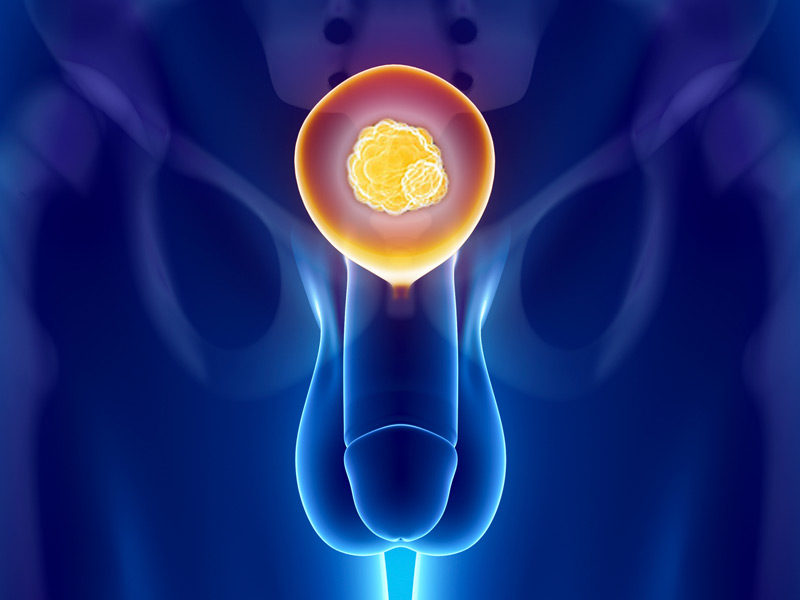

-Καρκίνος του προστάτη

Ο καρκίνος του προστάτη αναπτύσσεται στην εξωτερική ζώνη του προστάτη. Δεν απαιτεί πάντα ο καρκίνος του προστάτη χειρουργική επέμβαση, που έχει πολλές παρενέργειες, όπως ακράτεια ούρων και σεξουαλική δυσλειτουργία από την βλάβη των νεύρων που ελέγχουν την στύση και βρίσκονται δίπλα στον προστάτη. Η ζωή είναι δική σας κι εσείς θα αποφασίσετε τι θεραπεία θα κάνετε, αλλά σίγουρα πρέπει να παρακολουθήστε συχνά, αλλά όταν αποφασίσετε πια θεραπεία θα κάνετε, θα πρέπει να έχετε υπόψη σας το προσδόκιμο επιβίωσης, την ποιότητα ζωής σας, τις παρενέργειες της θεραπείας και την επιθετικότητα του καρκίνου. Οι ογκολόγοι και ουρολόγοι χρησιμοποιούν την κλίμακα Gleason για να προσδιορίσουν πόσο επιθετικά είναι τα κύτταρα, αλλά εσείς κάντε και ένα μοριακό προφίλ του όγκου για να είστε σίγουροι!!!